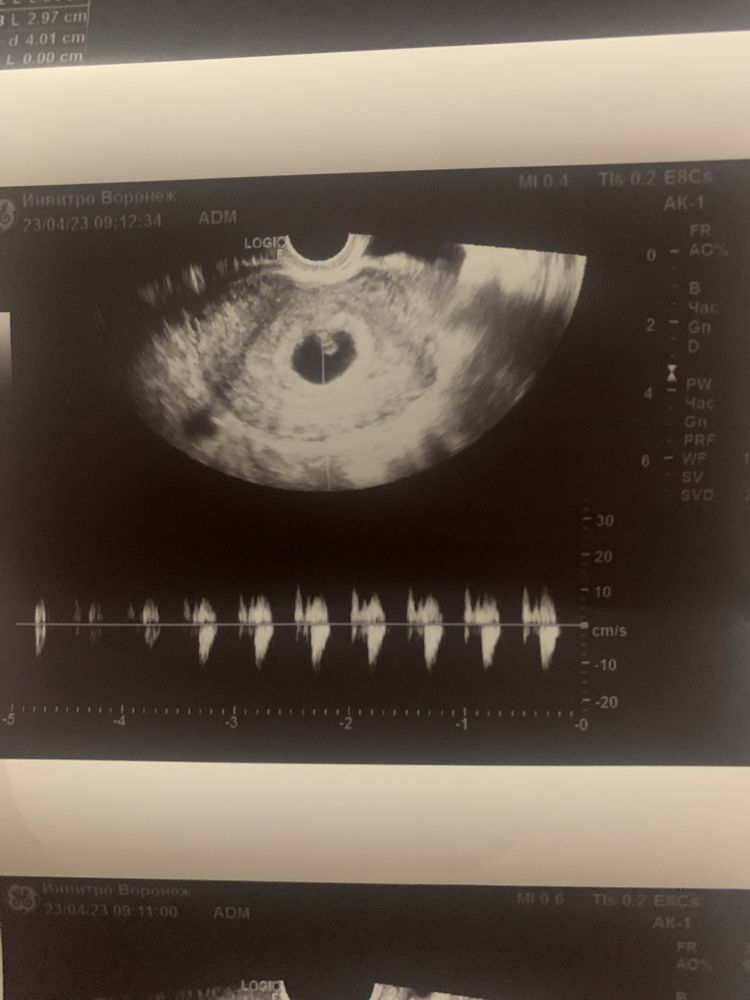

подскажите как быть ?! Стараюсь не думать и сохранять спокойствие , ходила на узи сказали 6.1 неделя , но отсутвует желтого мешочка( дословно не помню ) прописали прогестерон по 10 мг два раза в день - пью ! Сдаю кровь регулярно смотрю динамику хгч в 6.4 недели показатель - 64тыс , в 7 недель - 102 тыс , завтра 7,6 недель почти 8 пойду еще раз сдам на прием только 15 мая , сильный токсикоз ) чем чревато отсутствие желтого (мешочка) ?? Мне сказали что могут быть серьезнейщие патологии развития плода

Так на фото желточный мешочек есть,вы наверное путаете с желтым телом,а это вообще разные вещи

Непонятно о чём речь - о желточном мешочке или жёлтом теле? Скиньте текстовый протокол УЗИ! Там где написано про плодное яйцо и яичники..